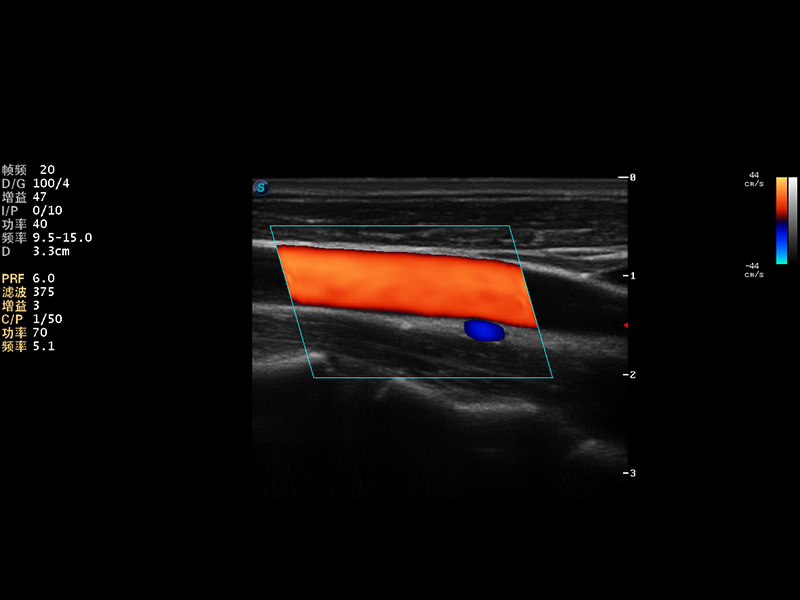

AutoC智能血流追踪